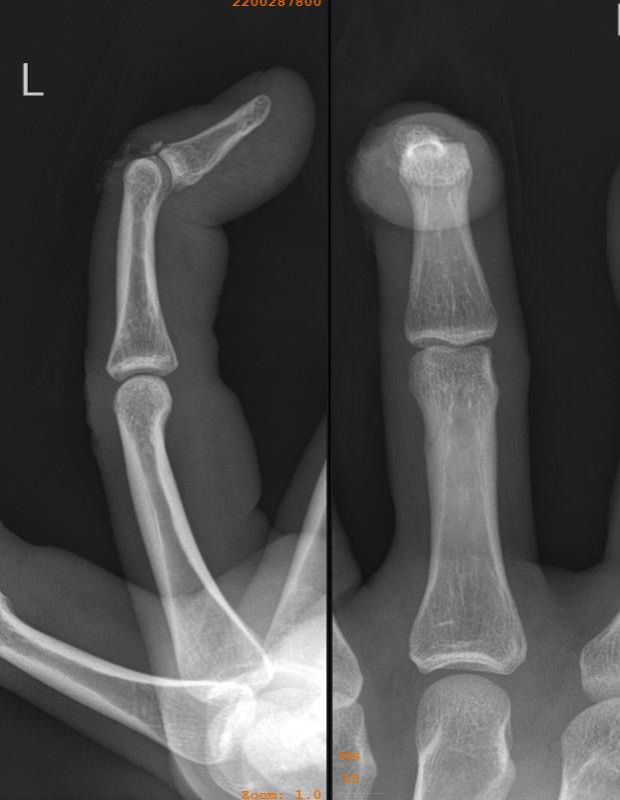

Mallet finger Image

from radiopaedia.org